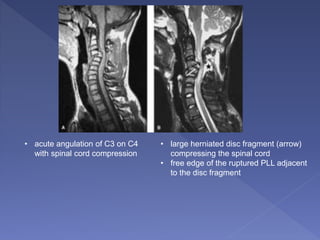

• acute angulation of C3 on C4

with spinal cord compression

• large herniated disc fragment (arrow)

compressing the spinal cord

• free edge of the ruptured PLL adjacent

to the disc fragment